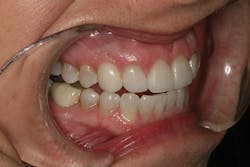

After approval of the diagnostic wax-up, profound anesthesia in the area of Nos. 6 through 11 was achieved (Septocaine, Septodont). Following sounding for bone to confirm adequate biologic width, laser soft-tissue recontouring in the areas of Nos. 6 through 11 was performed using an Er;Cr:YSGG soft- and hard-tissue laser (Waterlase, Biolase). Teeth Nos. 7, 8, 9, and 10 were prepared for conventional porcelain laminate veneers. Implant crowns were sectioned and removed from Nos. 6 and 11 (figure 4). To verify the radiographic implant identification, the abutments were removed and impression copings were tried in and radiographic seat was confirmed. The abutments were then replaced to serve as provisional restorative components. Screw access holes were blocked out and the provisional stent was used to fabricate provisional restorations on Nos. 6 through 11 (Luxatemp Ultra BL, DMG America) (figures 5, 6).

Figure 4

Figure 5

Figure 6